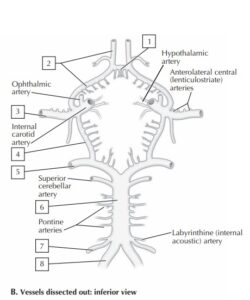

4. Arteri yang membentuk hubungan antara A. carotis interna kanan dan kiri adalah: (struktur no. 1)CorrectIncorrect -

8. Cabang oftalmika (A. ophthalmica) merupakan cabang dari:

9. Seorang laki-laki, 60 tahun, mengalami sumbatan pembuluh darah otak. Dari hasil pemeriksaan ditemukan adanya sumbatan pada arteri cerebri anterior dan arteri communicans. Dokter menjelaskan bahwa

gejala menjadi lebih ringan karena adanya suplai darah dari arteri lain dari circulus willisi ,Pada gambar di bawah, nomor berapakah yang menunjukkan letak sumbatan pembuluh darah tersebut? CorrectIncorrect